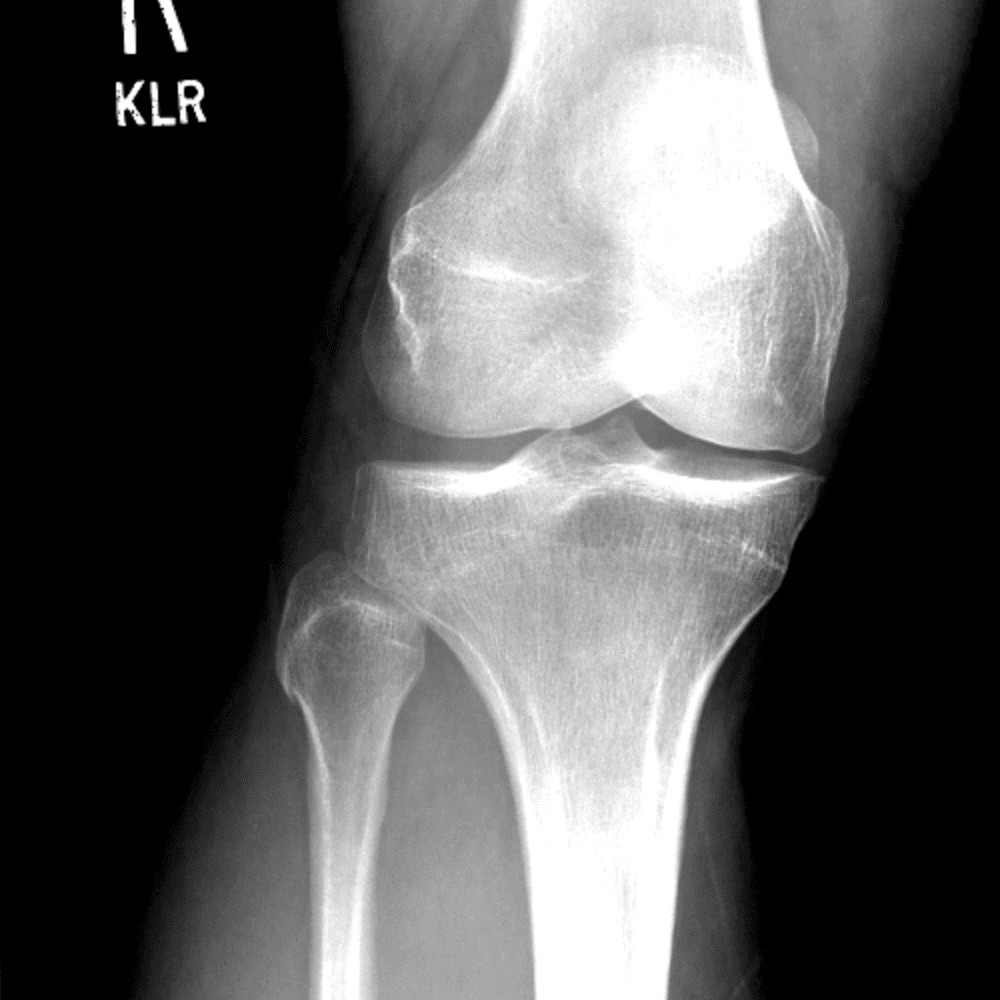

Simula o plantão incluindo casos sutis ou difíceis e alguns normais.